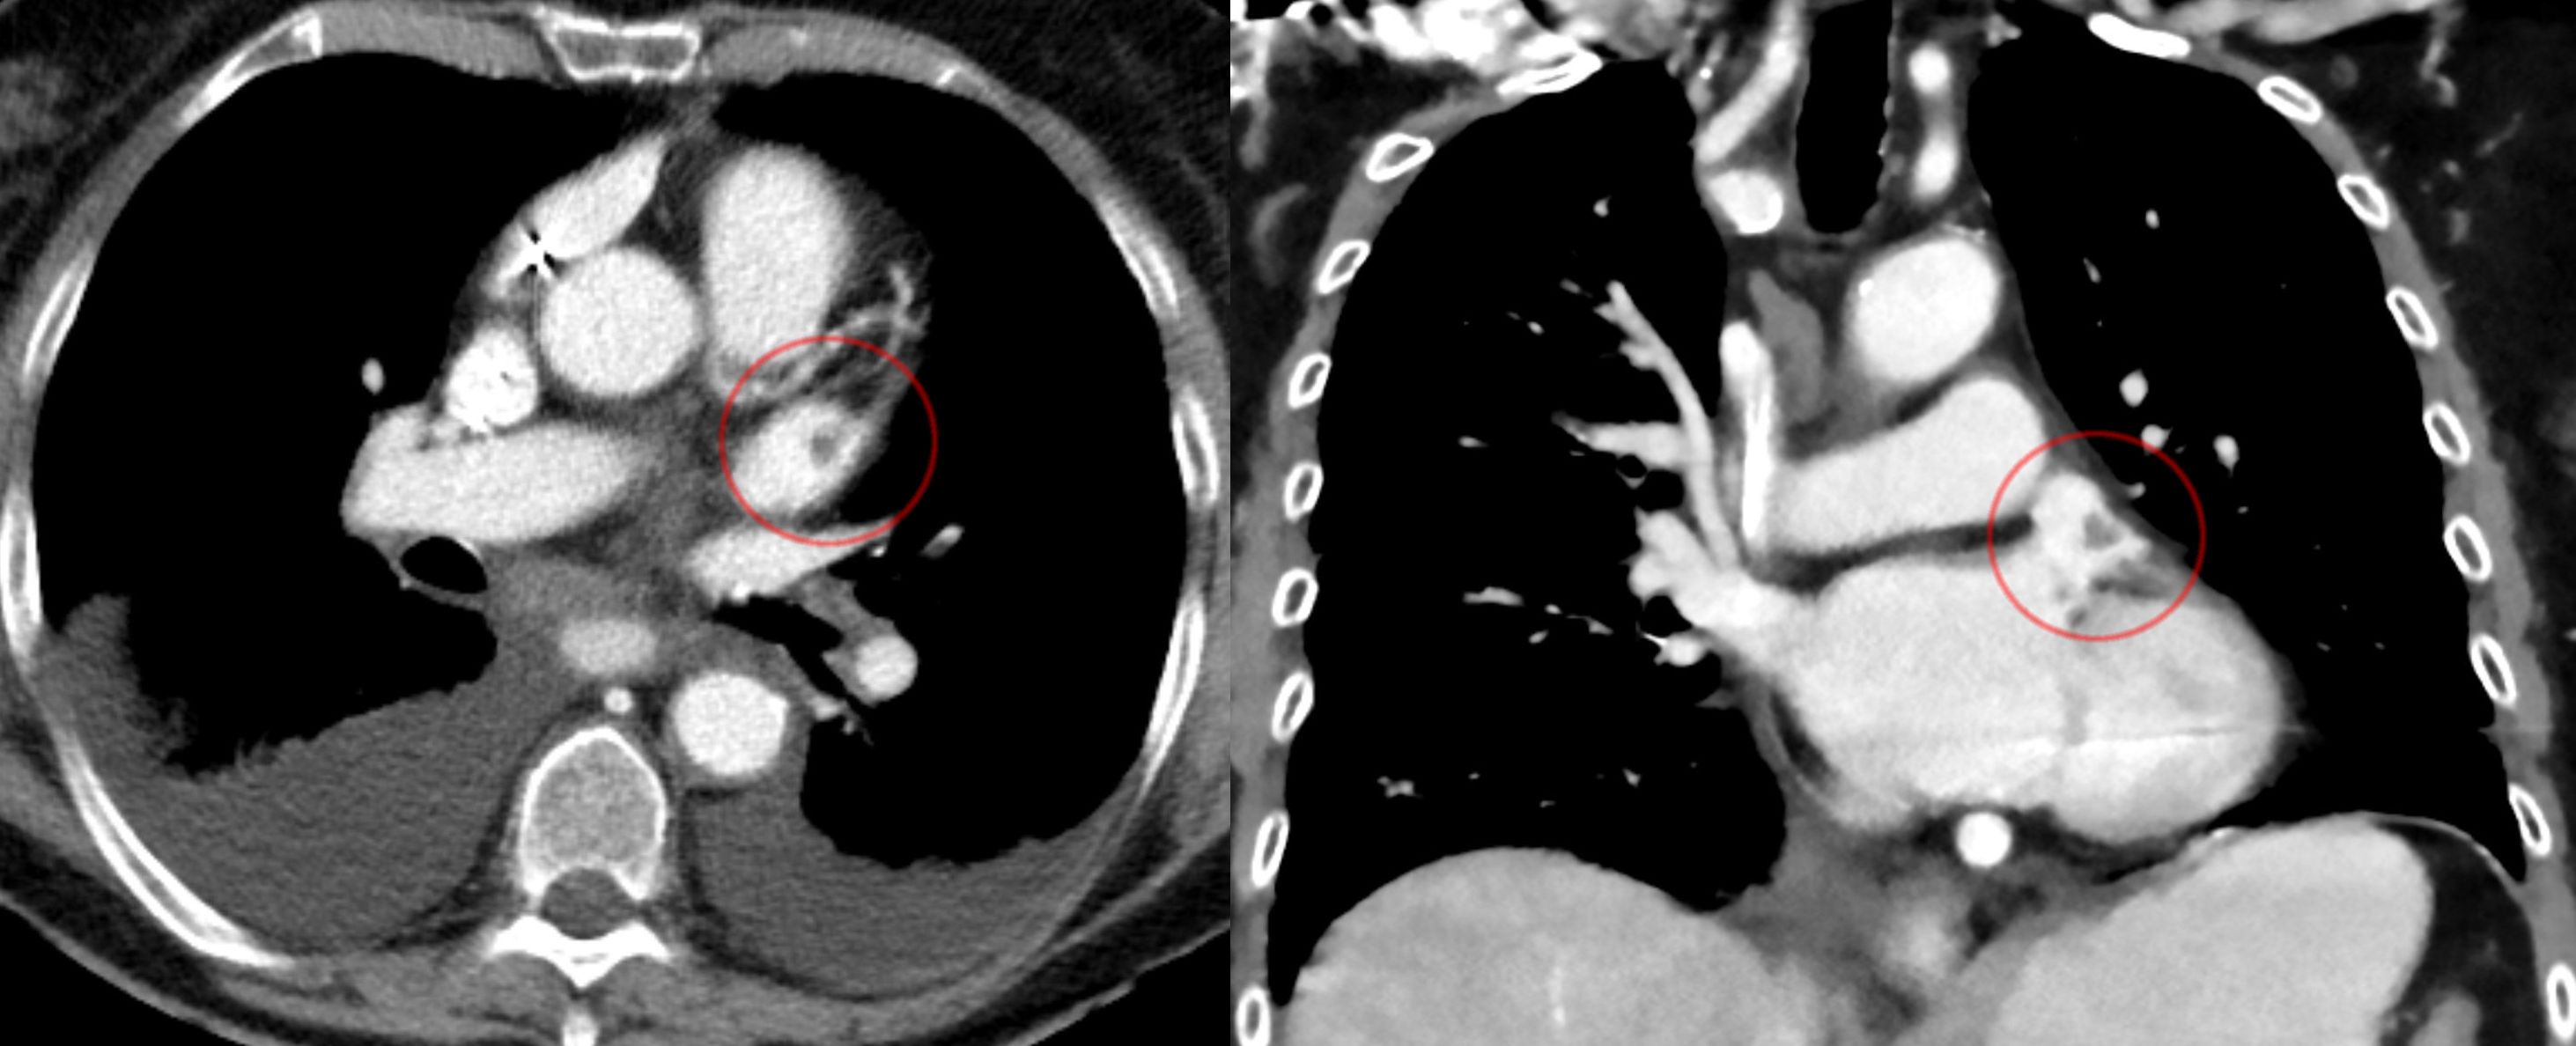

좌심방의 윗부분에는 근육질의 귀 모양 주머니, 즉 '''좌심방이'''('''LAA''', auricula atrii sinistra|아우리쿨라 아트리 시니스트라la)가 있는데, 이는 튜브 모양의 소주 구조를 가지고 있다.[9] CT 스캔으로 본 좌심방이(LAA) 해부학적 구조는 닭 날개형(48%), 선인장형(30%), 풍선형(19%), 콜리플라워형(3%)의 4가지 그룹 중 하나로 특징지어진다.[10][11] 콜리플라워형은 색전증과 가장 자주 연관되는 형태이다.[11] 좌심방이는 "좌심실 수축기 및 좌심방 압력이 높을 때 감압 챔버 역할을 한다"고 여겨진다.[12] 또한 나트륨 이뇨 펩타이드인 심방 나트륨 이뇨 펩타이드(ANP)와 뇌 나트륨 이뇨 펩타이드(BNP)를 관상 정맥동으로 분비하여 혈관 내 용적을 조절하며, 여기서 혈액 순환으로 들어간다.[13]

좌심방이의 몸체는 좌심방 앞쪽에 위치하며 좌측 폐정맥과 평행하다. 좌측 폐동맥은 후상방으로 지나가며, 가로동에 의해 심방이와 분리된다.[17] 심방 세동에서[13] 좌심방이는 수축하는 대신 세동하여 혈액 정체를 유발하고, 이는 혈전의 형성을 촉진한다.[9] 그로 인한 뇌졸중 위험 때문에 외과 의사는 개심 수술 중에 좌심방이 폐쇄 시술을 사용하여 좌심방이를 폐쇄할 수 있다.[18]

심방 세동, 승모판 질환 및 기타 질환이 있는 환자의 경우, 좌심방 이개에 혈전이 형성되는 경향이 있다.[12] 혈전이 떨어져 나가(색전) 전신 순환에 의해 공급되는 뇌, 신장 또는 기타 장기에 허혈성 손상을 일으킬 수 있다.[29]

조절되지 않는 심방 세동이 있는 환자의 경우, 이개 내 향후 혈전 형성을 방지하기 위해 모든 개심 수술 시 좌심방 이개 폐쇄술을 시행할 수 있다.[30]

7. 관련 질환

좌심방의 윗부분에는 근육질의 귀 모양 주머니, 즉 '''좌심방이'''('''LAA''')가 있는데, 이는 튜브 모양의 소주 구조를 가지고 있다.[9] CT 스캔으로 본 LAA 해부학적 구조는 닭 날개형(48%), 선인장형(30%), 풍선형(19%), 콜리플라워형(3%)의 4가지로 분류할 수 있다.[10][11] 이 중 콜리플라워형은 색전증과 가장 자주 연관된다.[11] LAA는 좌심실 수축기 및 좌심방 압력이 높을 때 감압 챔버 역할을 하며, 심방 나트륨 이뇨 펩타이드(ANP)와 뇌 나트륨 이뇨 펩타이드(BNP)를 관상 정맥동으로 분비하여 혈관 내 용적을 조절한다.[12][13]

좌심방이는 표준 후전방 X-레이에서 좌측 폐문 하단이 오목하게 나타나는 것이나 경식도 심장 초음파 검사를 통해 확인할 수 있다.[14][15] 좌심방이는 승모판 수술에 접근하는 통로로 사용될 수 있다.[16] 좌심방이의 몸체는 좌심방 앞쪽에 위치하며 좌측 폐정맥과 평행하고, 좌측 폐동맥은 후상방으로 지나가며, 가로동에 의해 심방이와 분리된다.[17]

심방 세동에서[13] 좌심방이는 수축하는 대신 세동하여 혈액 정체를 유발하고, 이는 혈전의 형성을 촉진한다.[9] 뇌졸중 위험 때문에 외과 의사는 개심 수술 중에 좌심방이 폐쇄 시술을 사용하여 좌심방이를 폐쇄할 수 있다.[18] 성인에서 심방 중격 결손은 혈액이 좌심방에서 우심방으로 흐르게 하여 심박출량을 감소시키고, 잠재적으로 심부전을 일으키며, 심각하거나 치료하지 않은 경우에는 심정지 및 급성 심장사를 유발할 수 있다.

심방 세동, 승모판 질환 및 기타 질환이 있는 환자의 경우, 좌심방 이개에 혈전이 형성되는 경향이 있다.[12] 혈전이 떨어져 나가(색전) 전신 순환에 의해 공급되는 뇌, 신장 또는 기타 장기에 허혈성 손상을 일으킬 수 있다.[29] 조절되지 않는 심방 세동이 있는 환자의 경우, 이개 내 향후 혈전 형성을 방지하기 위해 모든 개심 수술 시 좌심방 이개 폐쇄술을 시행할 수 있다.[30]